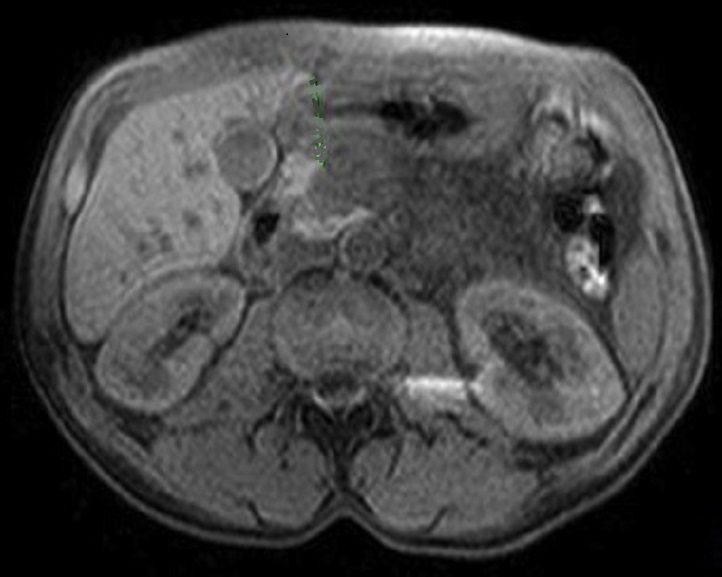

Image radiologique Wirsungo-

cholangio IRM ( Bili -IRM ) d'une adenocarcinoma de

la tete du pancreas en presence comme une ostacle de

la conduit de CPP ( canal pancreatique principale ) . Le canal

principal du pancreas en amont est dilate et voie

biliaire principale est encore en vue legerement

distendue |

Une autre cas de tumeur

cephalique du pancreas . Le canal pancreatique

principale en amont est dilate marque ( fleche rouge ) .

Image radiologique Wirsungo - cholangio IRM . |